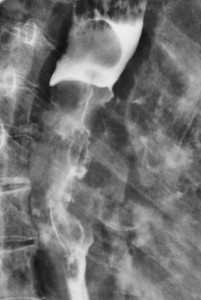

Метастазы в легких — фото рентгенограммы. Округлые тени — метастазы рака пищевода. Хорошо виден большой узел округлой формы вблизи переднего отрезка 2-го ребра. На снимке справа - циркулярное сужение пищевода за счет опухолевого утолщения его слизистой оболочки.